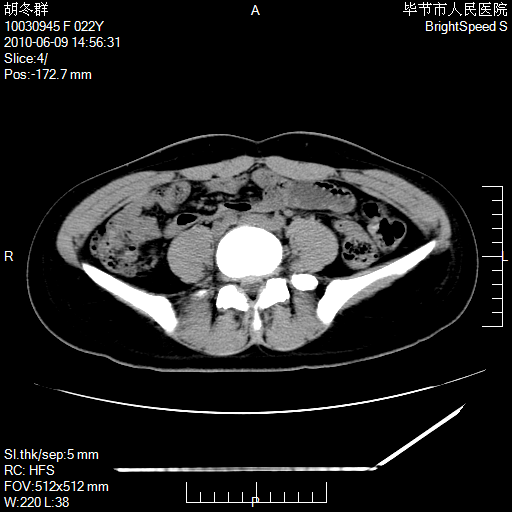

患者23岁,发现腹部包块3月。

盆腔内囊性占位;穿刺或者直接手术拿掉即可,不必紧张。

左侧卵巢囊腺瘤或囊腺癌

盆腔内囊性占位性病变;考虑左侧卵巢囊腺瘤。

有分隔、壁薄,支持考虑左侧卵巢囊腺瘤。

左侧卵巢浆液性囊腺瘤。

支持左侧附件区囊性占位,多考虑为囊腺瘤。

支持考虑左侧卵巢囊腺瘤;宫腔积液。

有分隔、壁薄,支持考虑左侧卵巢囊腺瘤。排尿后,膀胱缩小,由于重力作用,肿块下移就到了膀胱位置,很好理解。